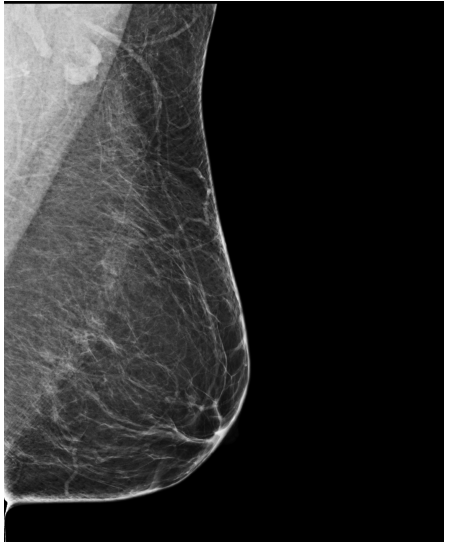

Refer to caption

(a) FeatAlign

(b) FeatAlignReg

(c) ImgFeatAlign/ImgAlign

(d) FeatAlign

(e) FeatAlignReg